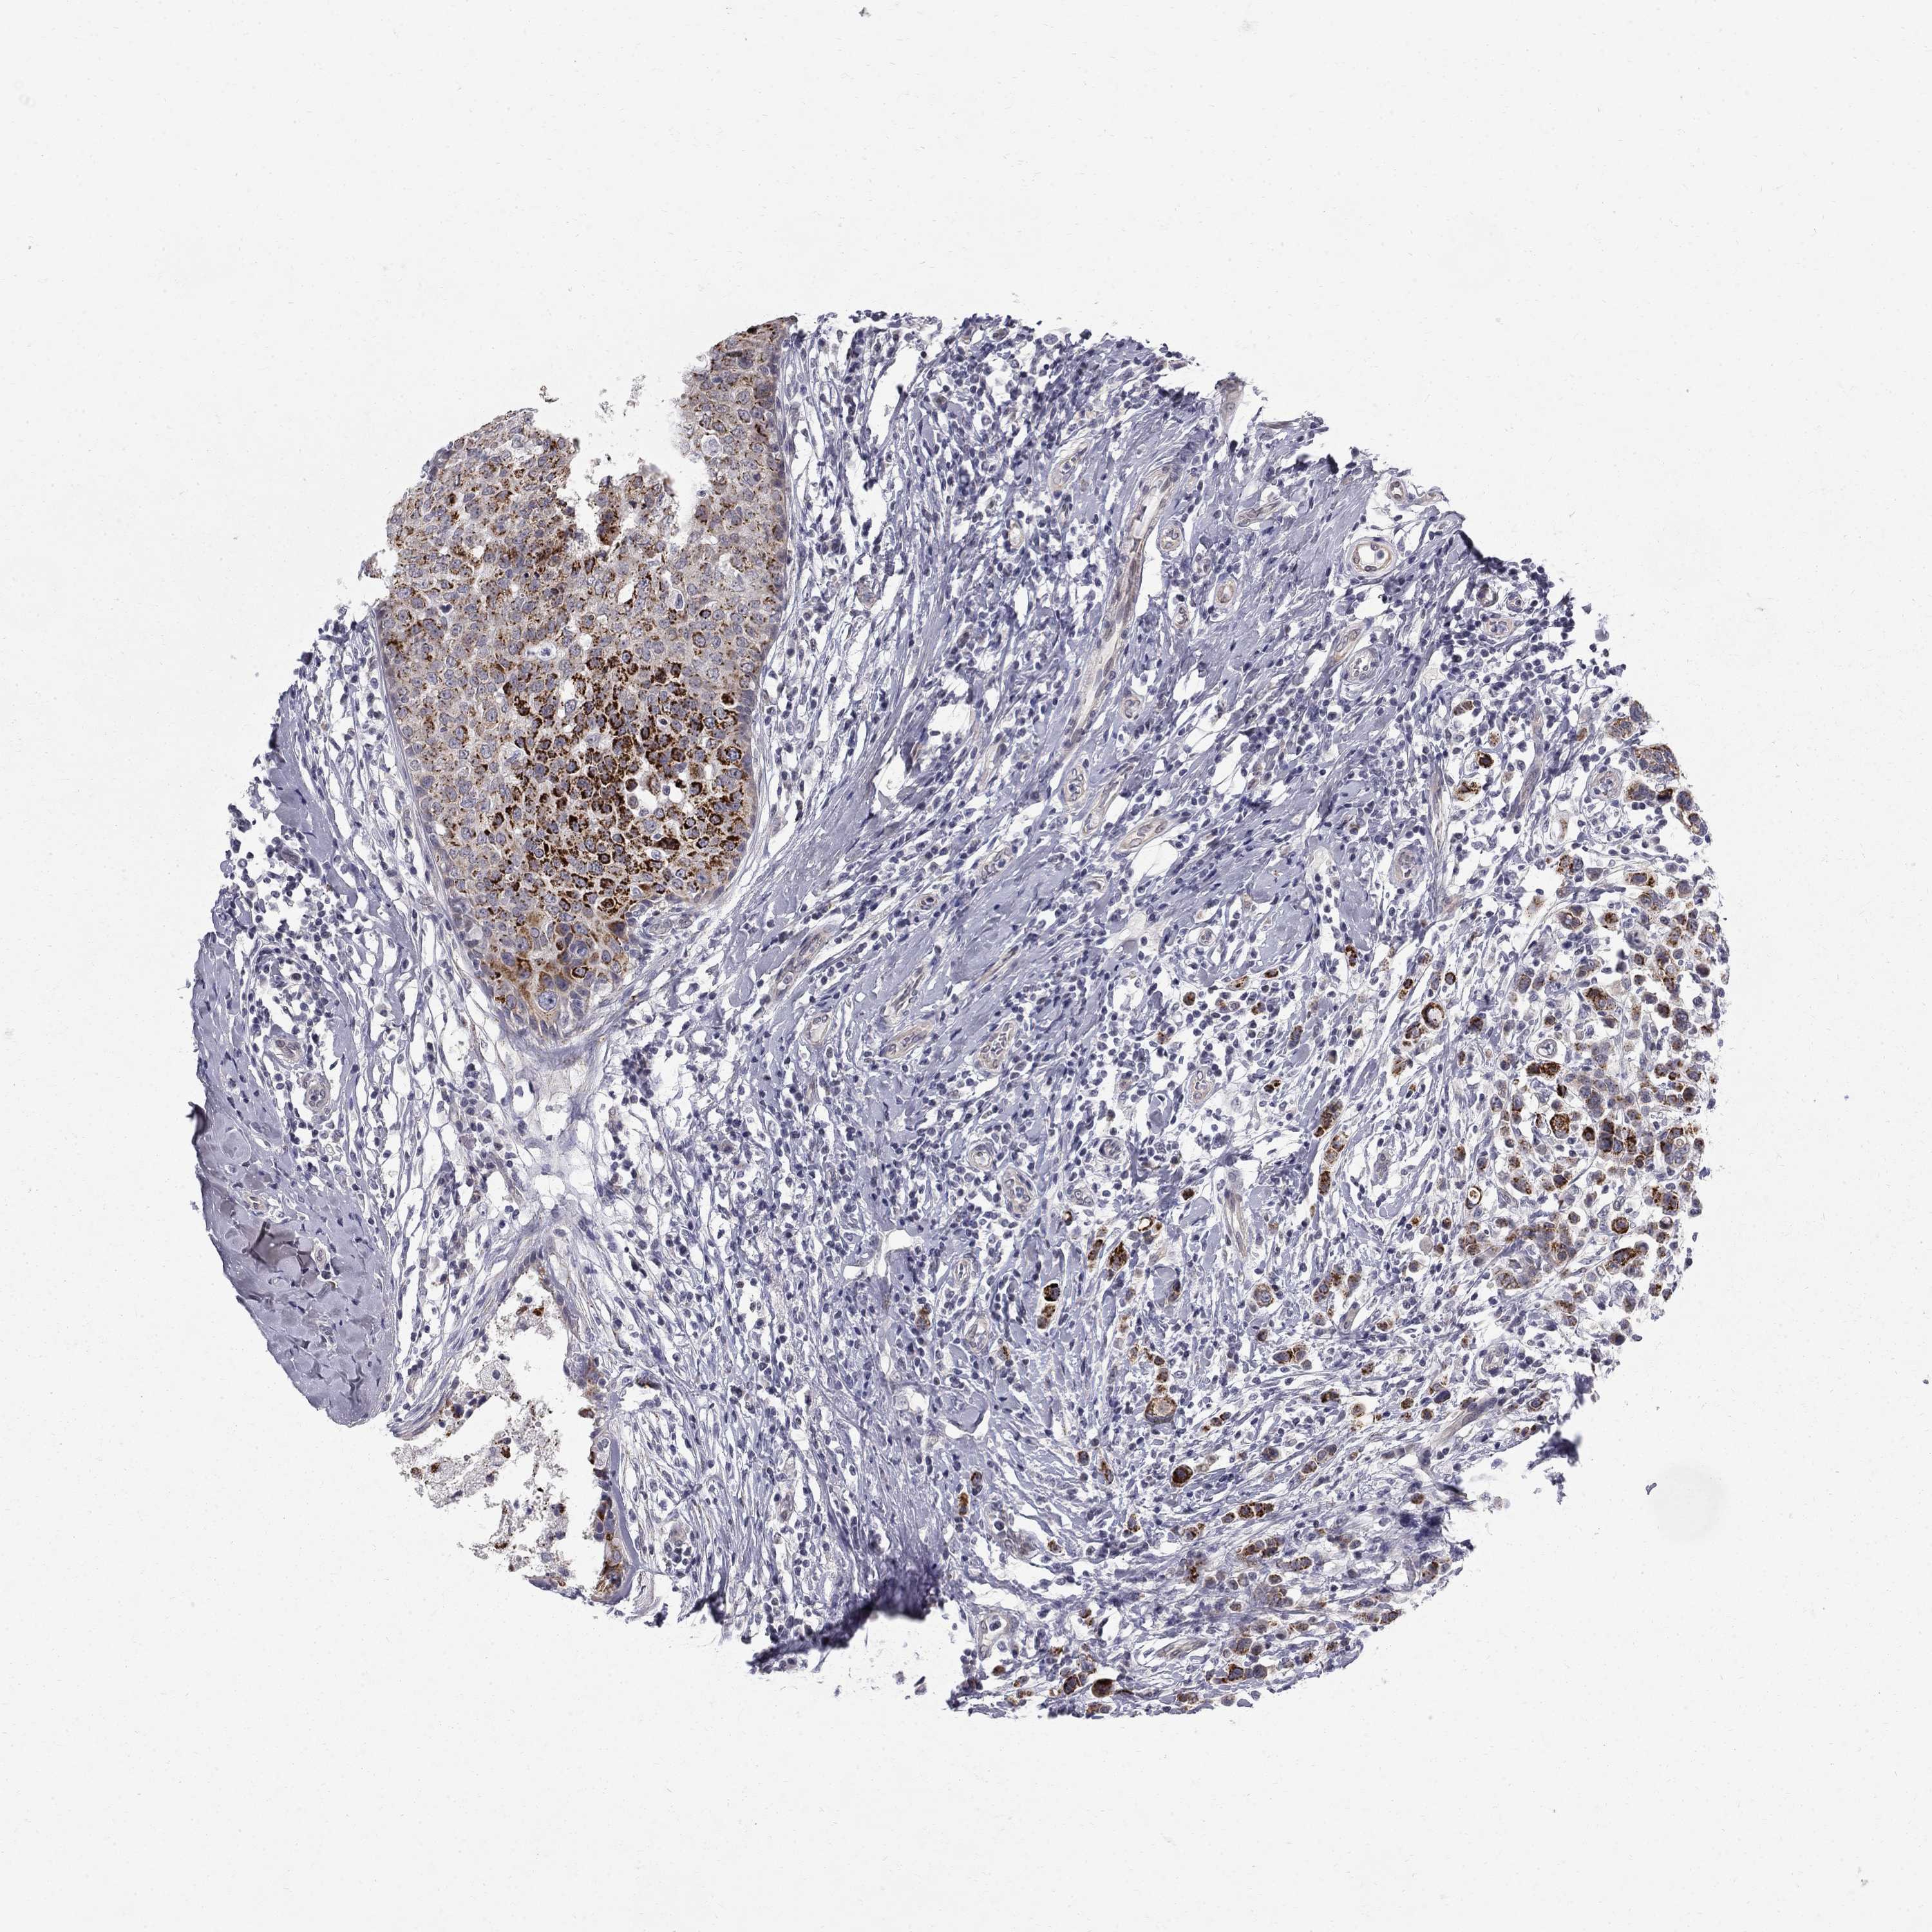

BRCA TCGA BRCA VALIDATION PROTEIN EXPRESSION